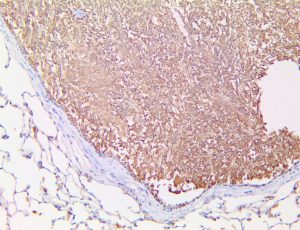

The first cytokines released are interleukin 1β (IL-1β) and tumor necrosis factor-α (TNF-α), which attract a variety of circulating white blood cells (WBCs) to the infection site, including neutrophils, monocytes, macrophages, and natural killer (NK) cells. This response, along with the antipathogenic chemicals released by these cells (i.e., complement), comprise the innate immune response. These cells directly attack the invading pathogen and also release additional cytokines, chief among them interleukin-1 and 6 (IL-6). IL-6 is essential for invoking the adaptive immune response, which calls T-cells, B-cells, and T helper (Th) cells to the infection site. IL-6 also stimulates further recruitment, proliferation and activation of macrophages.

It is the ICU physician who is most likely to witness one of the deadliest manifestations of the abnormal immunological response, the cytokine storm syndrome (CSS). This response is also referred to by some as the cytokine release syndrome (CRS). CSS is characterized by continuous activation and expansion of macrophage and lymphocyte populations, which secrete large amounts of cytokines, causing the cytokine storm. This massive cytokine release is akin to hemophagocytic lymphohistiocytosis (HLH) disease, a syndrome characterized by initial unchecked and persistent activation of cytotoxic T lymphocytes and NK cells.

This activation induces inflammatory monocytes to highly express IL-6, starting a localized and then systemic cascade effect that results in hyperproduction of IL-6, which accelerates the inflammatory process. Because IL-6 also increases vascular permeability, excessive levels cause blood vessels to become very leaky. This, along with clotting factors released from vascular endothelial cells, stimulates the coagulation cascade, resulting in microthrombosis (tiny clots), which leads to ischemia and tissue death of the kidney, intestines, heart, liver, brain and extremities.